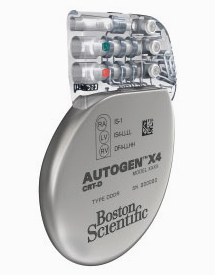

Pacemakers

Pacemakers are most commonly required for patients with a history of collapse or dizzy spells, when ECG monitoring shows that this is due to a slow heart rate. A pacemaker comprises of two main components, the "pacemaker box" which contains a battery and electrical circuit, and the pacing leads (usually one or two leads are required) which are passed along a blood vessel to the heart. The wires can sense when the heart beats normally and if the heart beats too slowly they can produce an electrical impulse to stimulate the heart. The pacemaker box is usually sited under the skin on the upper chest below the collar bone. The procedure is performed under local anaesthesia with sedation if needed. Patients usually need to stay one night in hospital.

A new type of pacemaker, known as a biventricular pacemaker or cardiac resynchronisation therapy is available for certain patients with heart failure. This usually requires 3 leads and improves the timing of the heart which usually leads to improved quality of life and has been shown to prolong life. These pacemakers are only suitable for certain individuals.

Another form of specialist pacemaker called an implantable cardiac defibrillator (ICD) can be implanted in patients who have survived a cardiac arrest or in patients who have had ventricular arrhythmias (fast heart rhythms from the bottom chambers of the heart). The lead detects abnormal rhythms and depending on how the device is programmed the ICD can try to rapidly pace the heart to stop the arrhythmia but if that is not effective it will then shock the heart to restore a normal heart rhythm. An ICD can be combined with a biventricular pacemaker (BiV-ICD) in selected patients with severe heart failure to improve symptoms and improve mortality.